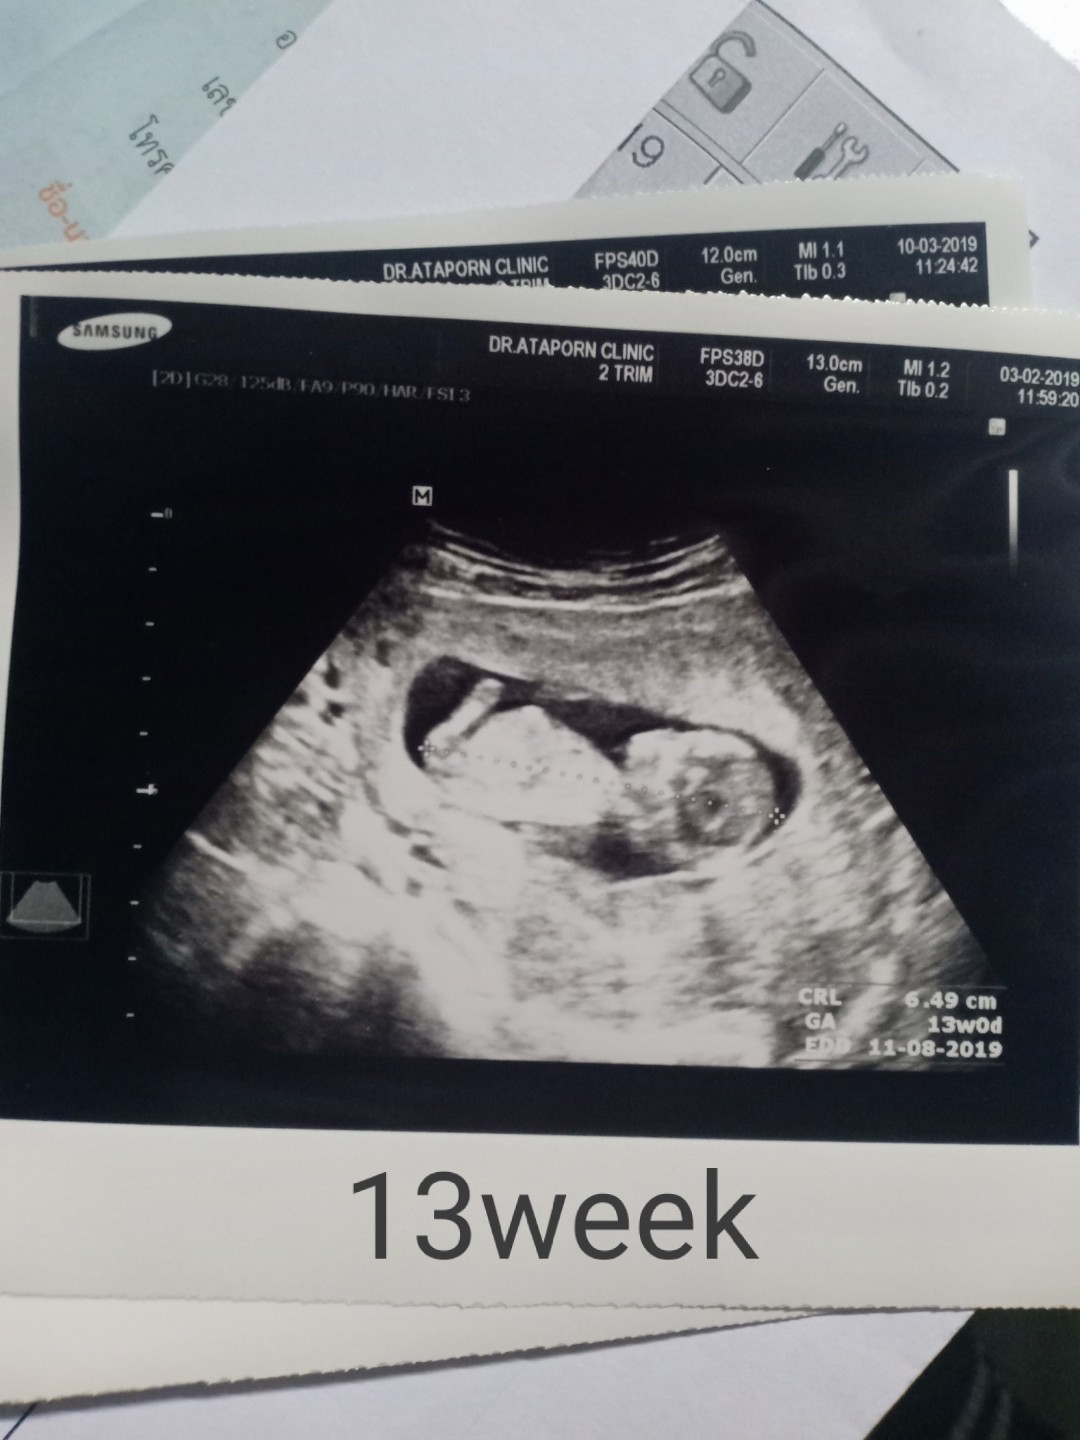

ตอน13w ค่ะ

13 วีคค่ะ